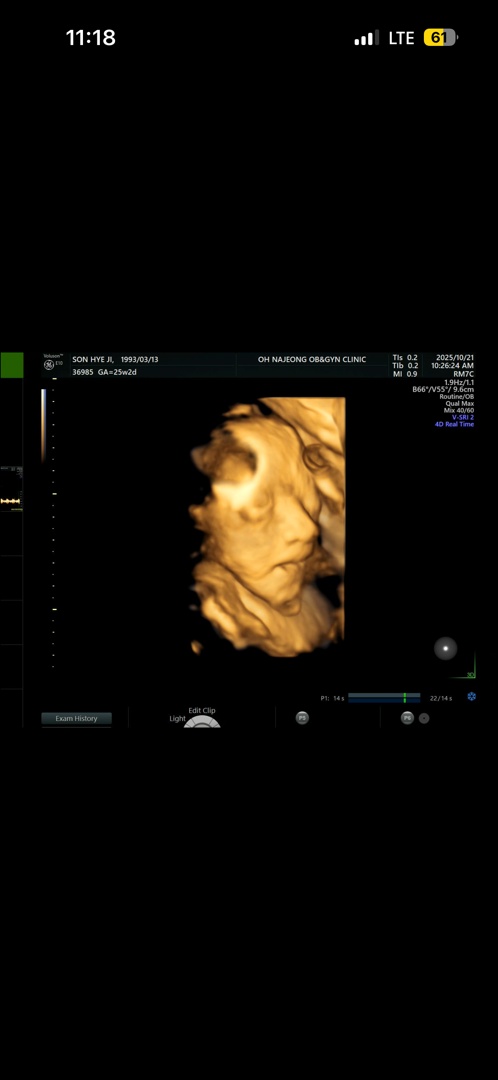

25주차 아빠입니다!! 저번에는 얼굴 가려서 아기 얼굴을 못봤는데 오늘 처음으로 얼굴을 보여주더라구요 근데 딱 보자마자 코만 보이더라구요 ㅋㅋㅋ 다른 애기들 초음파 사진은 귀여운 애기 느낌인데 우리아들은 뭔가 어른같은 느낌?? 보통 태어나면 입체 초음파랑 비슷한가요?? 앞으로 얼굴이 또 많이 달라질까요??

25주차에도 살이 많이 안붙어있어서 거의 뼈라하더라구요~~ 그런데 코가 무척 높네요ㅋㅋ 코는 아빠라는데🫣

의사 선생님이 초음파 보면서 누구닮았지? 이러시다가 불키니까 아빠닮았네 이러시더라구요 ㅋㅋ